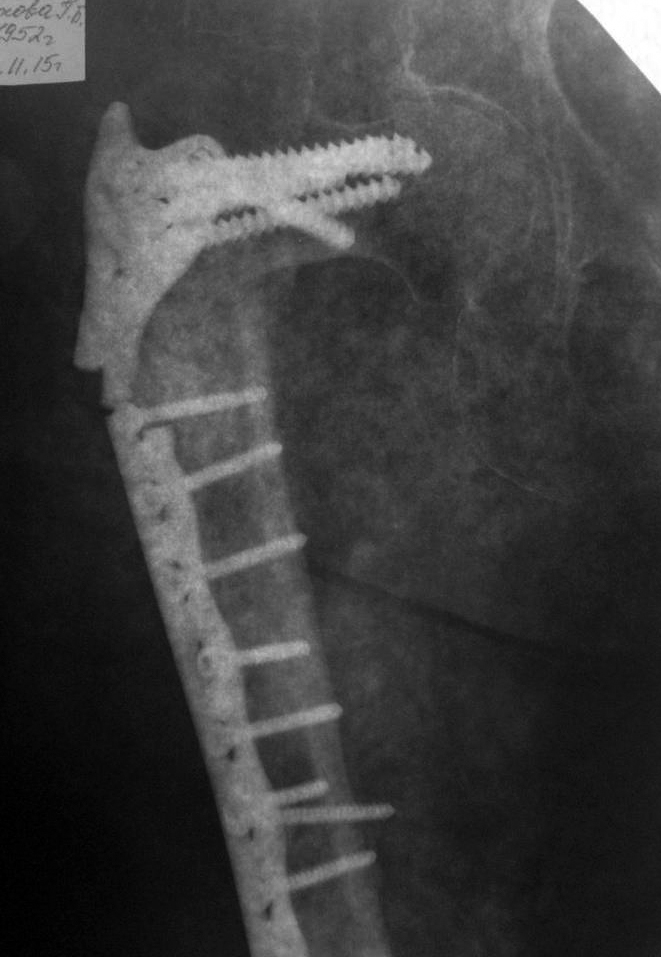

Здравствуйте, уважаемые коллеги! Прошу Ваших мнений по следующему случаю. Женщина 63г. Травма в январе 2013г, тогда же оперирована по поводу чрезвертельного перелома бедра DHS (снимки отсутствуют).

Зимой 2014-2015 без повторной травмы - перелом металлоконструкции и предположительно, повторный перелом бедра, повторная операция, с помощью металлоконструкции видимой на снимках (снимки послеоперационные отсутствуют).

3 недели тому - при сгибании бедра (стригла ногти) почувствовала хруст, выраженный болевой синдром, потеря опороспособности, рентгенологическая картина представлена.Сопутствующая патология: ревматоидный артрит с поражением суставов стоп, кистей. Принимает постоянно в течение нескольких лет метатрексат и преднизолон.

Анемия Hb-около 90 г/л. Планируемое лечение: 1.) отмена или снижение дозировок метатрексат, преднизолон.

3.) Оперативное лечениес удалением металлоконструкции и с использованием 3.1 )конструкции типа PFNA максимально возможной длины. 3.2) Предложен еще вариант эндопротезирования с длинным бедренным компонентом. Буду благодарен за участие в судьбе моей родственницы.